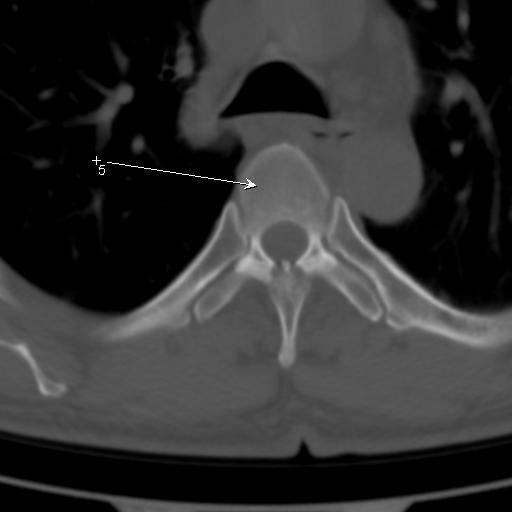

标题: CT25189:胸椎ct,请会诊!

既往食管癌,现行ct检查!

仅见椎体退行性改变

中上段食道癌,椎体轻度退变。

支持中上段食道癌,椎体轻度退变,必要时做ect。